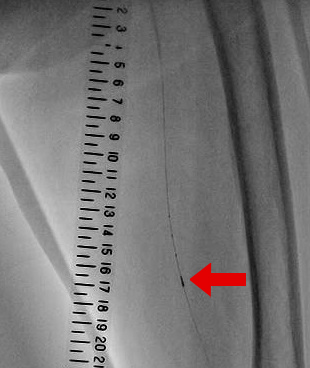

下肢動脈の病気を治療する方法です。下肢の重症虚血や間欠は行のある方の症状改善を目的に行います。下肢動脈の狭窄部分や閉塞部分に細い針金を通して、風船(バルーン)で病変を開大させます。体表からの超音波検査や血管内からの超音波検査と組み合わせて安全に治療していきます。

腎臓の機能が低下した方では、造影剤を使うことによってさらに腎臓の機能を悪くしてしまう危険があります。また、造影剤にアレルギー反応のある方も、重篤な副作用を引き起こす可能性があります。当院では通常使用する造影剤のほか、腎臓への負担を軽減するため、体に無害でアレルギー反応のない医療用炭酸ガスを用いて安全にカテーテル治療を行う技術があり、積極的に行っています。